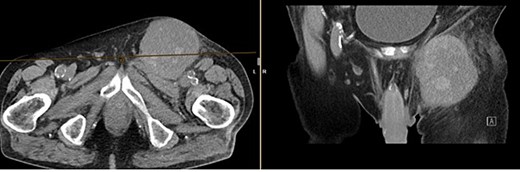

Further clarification was sought through a computed tomography (CT) scan of the entire abdomen (Fig. 1). The CT from 25 February 2022 showed an oval, encapsulated structure in the right groin area, most likely interpreted as a soft tissue hematoma. No active bleeding was observed. An enlarged lymph node was considered as a differential diagnosis. A follow-up CT on 1 August 2022 showed a size-progressive formation within the suspected right inguinal hernia compared with the previous examination in February (Fig. 2). There was no evidence of tumor recurrence or metastasis-suspect lesions intra-abdominally. A previous hysterectomy was also noted.

CT of the abdomen from 25 February 2022: oval encapsulated structure in the right groin area, most likely soft tissue hematoma, no active bleeding, DD enlarged lymph node.